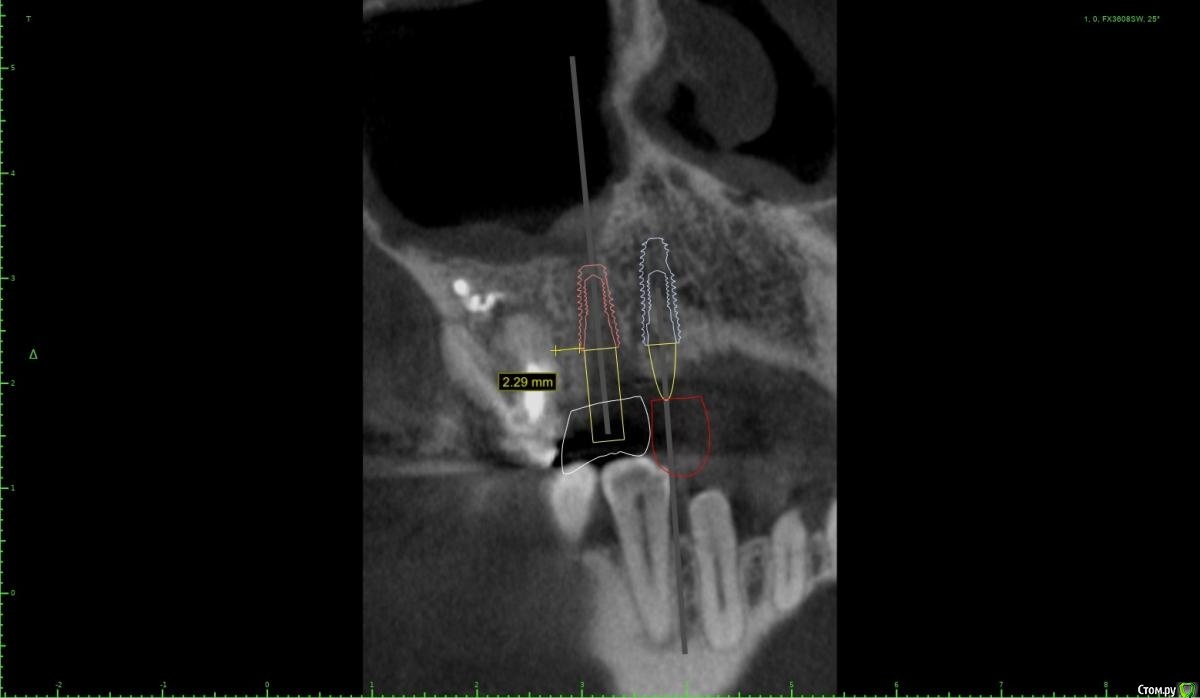

Женька Опубликовано 28 января, 2021 Поделиться Опубликовано 28 января, 2021 Что-то все спрашивают про консоли на имплантатах в области премоляров! Спрошу и я тоже.Коллеги как бы поступили в этом случае?Сам склоняюсь к консоли, но переживаю, что надо бы имплантат пошире, чтобы нагрузку нёс за двоих спокойно. Вариант с двумя винтами не нравится потому как тонковато (не очень) в области 1.4 и необходима редукция около 3мм кости. Ссылка на комментарий

Женька Опубликовано 1 февраля, 2021 Автор Поделиться Опубликовано 1 февраля, 2021 ИМХО два винта, но давайте с замерами тогдаДа, наверное вы правы, два по 3.6 проходят Ссылка на комментарий

Irouil Опубликовано 1 февраля, 2021 Поделиться Опубликовано 1 февраля, 2021 Я бы развел винты побольше, лучше ближе к зубам чем друг к другу, кроме того дистальный имплант можно сместить немного небнее Ссылка на комментарий

колесников Опубликовано 2 февраля, 2021 Поделиться Опубликовано 2 февраля, 2021 Два прекрасно проходят. Лучше имплант не агрессивный с микрорезьбой 3.5х8. Редуцировать грибком из набора даск. 14 сст вестибулярно и нагрузка на оба. Уступ абатмента взять 3мм коронки в основании заузить,вестибулярно балкон. Раскрывать хорошо бы роллом чтобы выделить сосочек,если сомневаетесь то внутрибороздковым и с 15 по палаччи выделить и перекинуть 1 Ссылка на комментарий